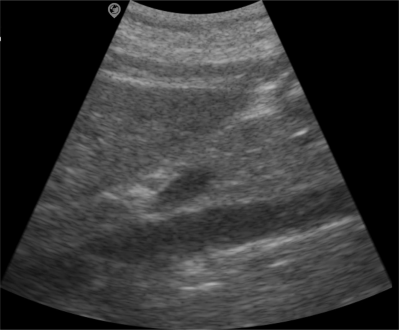

Brightness

The B-mode is a grayscale-modulated type that displays the intensity of tissue echo signals based on brightness levels, employing a multi-beam scanning method to form a two-dimensional grayscale image from each scan line. B-mode imaging provides two-dimensional cross-sectional views, offering real-time visualization of tissue structures with intuitive presentation. It is widely utilized in the diagnosis of various diseases across multiple clinical fields and remains the most extensively applied modality in current clinical practice.